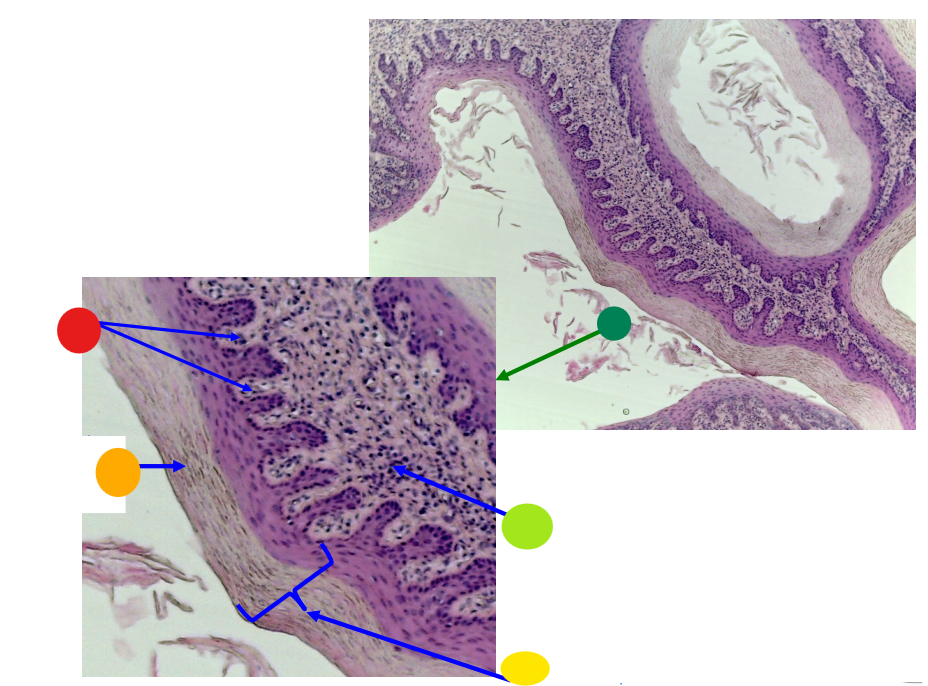

what is this?

ovary

red

primary oocyte

orange

zona pellucida

yellow

granulosa cells

light green

developing thecal cells

What is this

secondary follicle

red

granulosa cells

orange

primary or secondary oocyte

yellow

oocyte nucleus

light green

zona pellucida

dark green

cumulus oophorus

light blue

antrum

dark blue

thecal cells

what is this

tertiary follicle